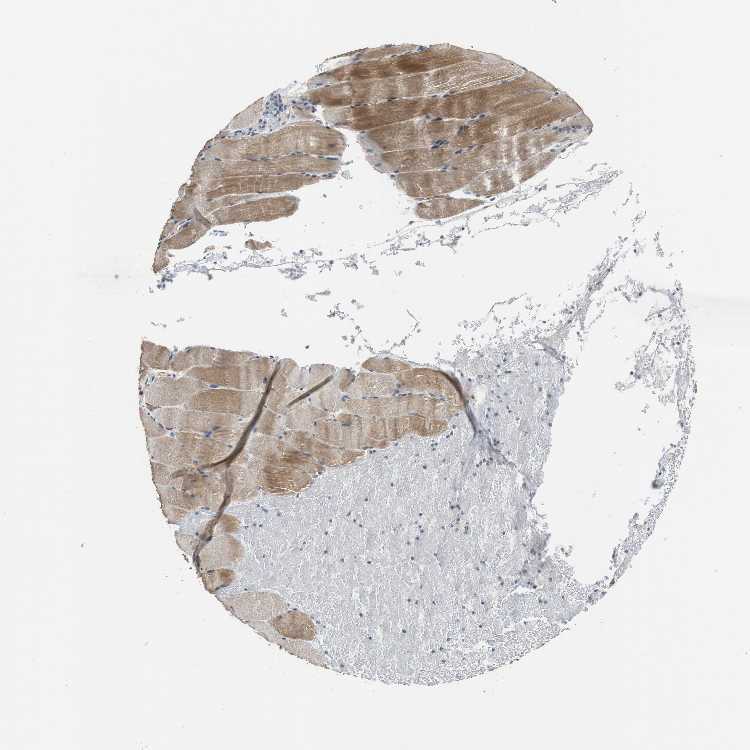

SKELETAL MUSCLE - Antibody stainingi

Antibody staining in the annotated cell types in the current human tissue is reported as not detected, low, medium, or high, based on conventional immunohistochemistry profiling in selected tissues. This score is based on the combination of the staining intensity and fraction of stained cells.

Each image is clickable and will lead to virtual microscopy that enables deeper exploration of all samples and also displays staining intensity scores, fraction scores and subcellular localization as well as patient and tissue information for each sample.

Antibody HPA006021

Myocytes Medium